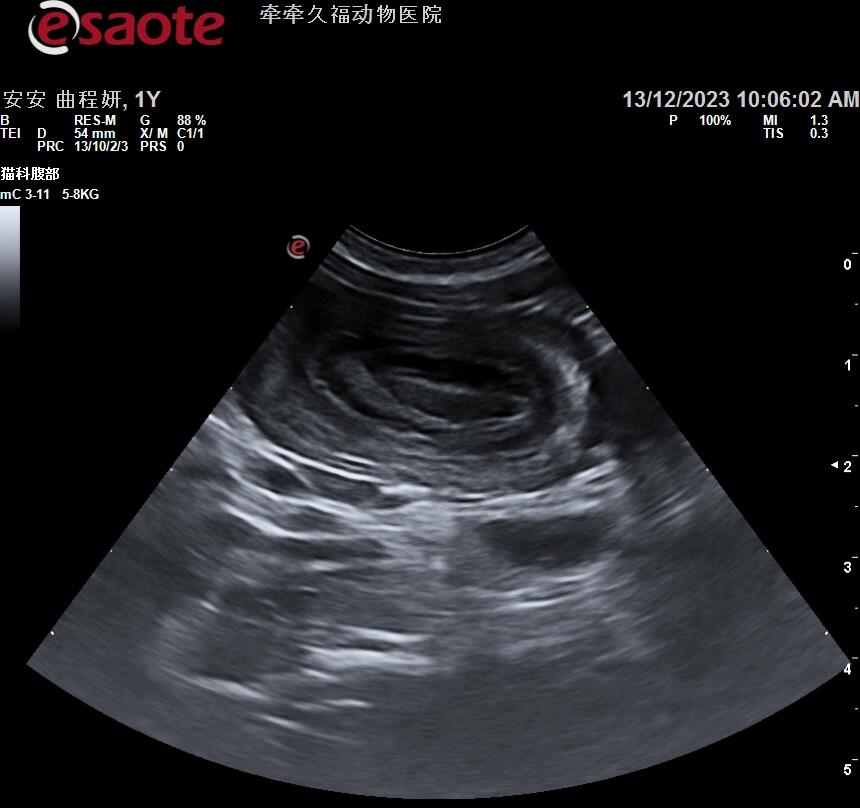

小儿腹盆腔疼痛超声之肠套叠

图片尺寸795x455